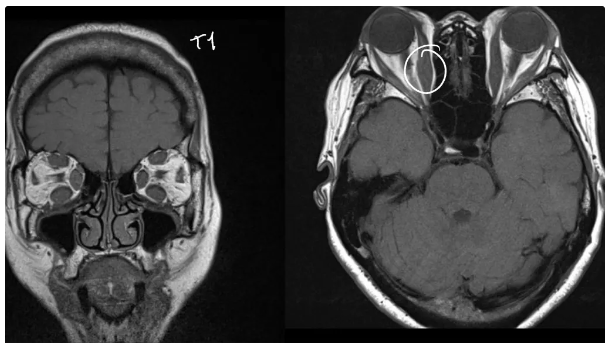

qué esperas ver en una TC por exoftalmos

protrusión ocular anormal, Disociación índice globo ocular-línea intercigomática (Si línea no cruza los ojos es anormal)

Qué esperas ver en una RM de exoftalmos

Protusion ocular anormal, Disociación índice ocular-línea intercantal y Masas ocupativas retroocular